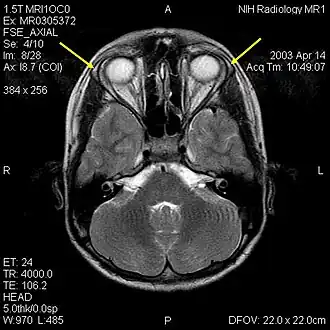

IRM du crâne d'un garçon de 12 ans présentant un syndrome Allgrove : les flèches jaunes indiquent les glandes lacrymales hypoplasiques.